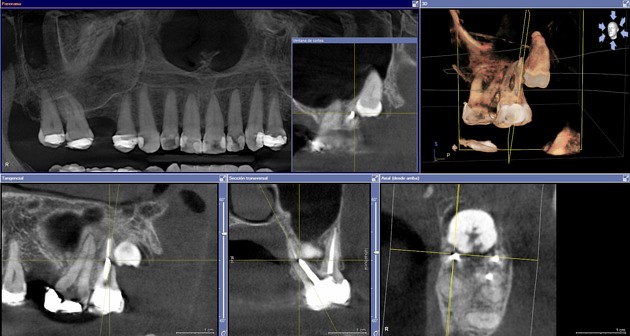

Cone Beam (CBCT)

Le cone beam dentaire (CBCT) est un examen d’imagerie 3D à faible dose permettant l’analyse précise des dents, mâchoires et structures maxillo-faciales.